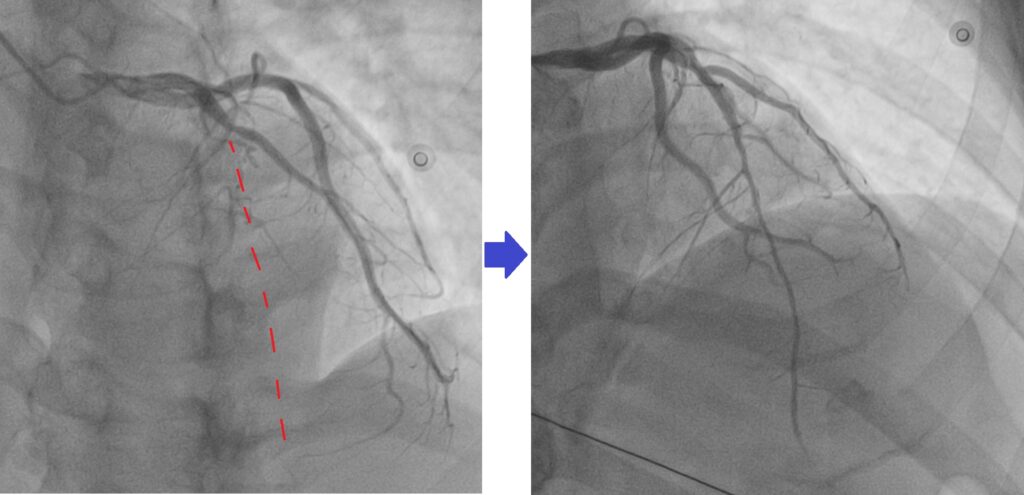

Example of my patient who has CTO LAD, there should be a vessel dictated by the red line. After opening the CTO, u can see coronary blood flow to the vessel.